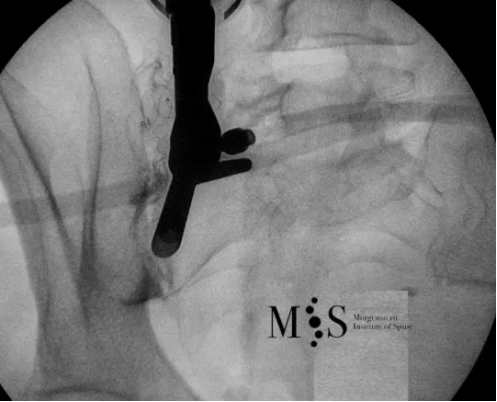

Imatge de fluoroscòpia intra-operatoria d’una endoscòpia de la articulació sacroiliaca.

Es pot veure com l’endoscopi está situat en el costat esquerre de la imatge asobre la articulació sacroiliaca